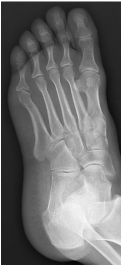

足骨

包括跗骨、跖骨和趾骨。跗骨共7块,分前、中、后列。后列包括距骨和跟骨;中列为距骨前方的足舟骨;前列为内侧楔骨、中间楔骨、外侧楔骨及跟骨前方的骰骨

跖骨,共5块,近端为底,与跗骨相接;中间为体,远端称头,与近节趾骨底相接

趾骨,共14块,踇趾为2节,其余各趾为3节。分为近节趾骨,中节趾骨和远节趾骨。每节趾骨近端为底,中间部为体,远端为滑车